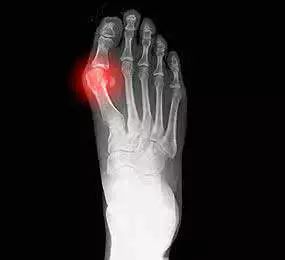

成都风湿医院收费贵不贵?痛风真的很可怕吗?

老年人是痛风这种疾病最主要的高发人群,并且老年人在患上这种疾病之后,很难能够彻底的治愈,所以这种疾病对老年朋友的身体健康,以及正常生活所带来的影响也是非常大的,那么痛风这种疾病真的有我们想象的那么可怕吗?我们一起来和成都风湿医院痛风科陈建春主任详细了解一下吧!成都风湿医院收费贵不贵?痛风真的很可怕吗?

成都治痛风较好的医院陈建春医生再一次为我们介绍了,人们在患上痛风这种疾病之后,会表现出来的一系列的症状表现,由于这种疾病给我们的身体带来的危害是大家不能忽视的,所以大家在生 活中除了要做好对这种疾病的预防工作之外,还要了解这种疾病的症状表现,这样在患病时才能把握较好治疗时间,尽快控制病情。